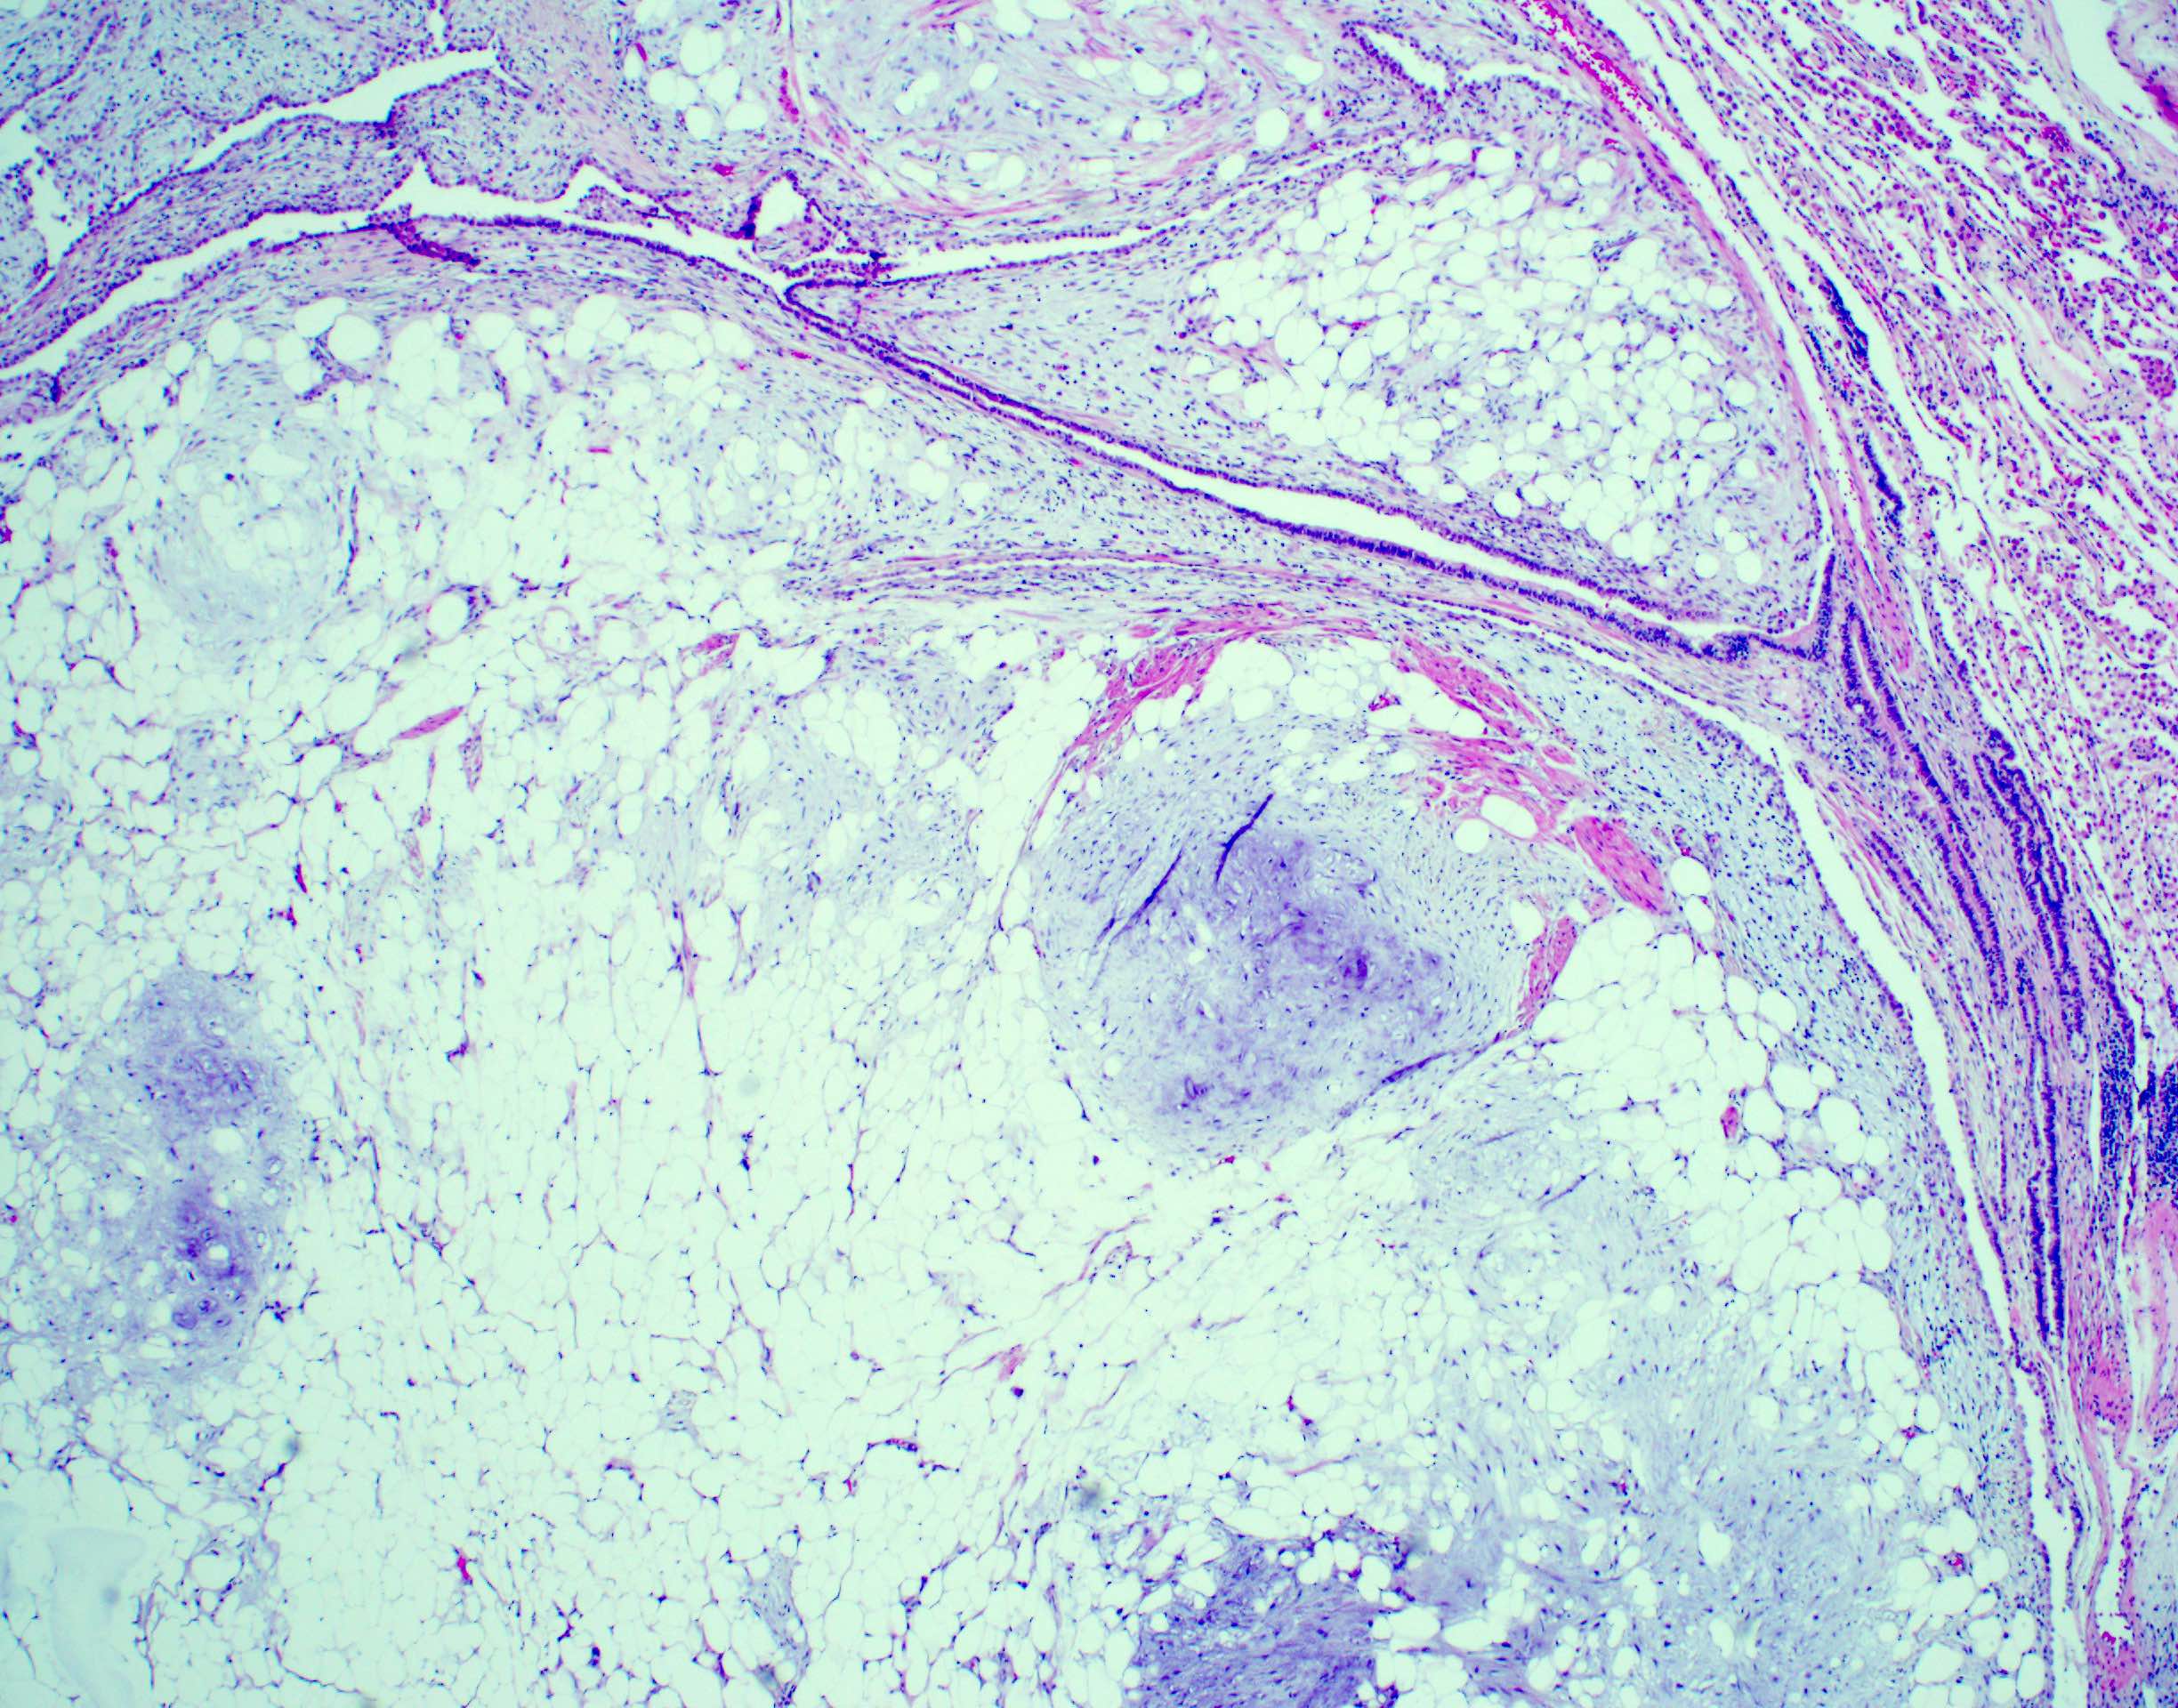

Microscopic (histologic) description

- Composed predominantly of varying degrees of mesenchymal tissue: hyaline cartilage, fat, smooth muscle and bone

- Other connective tissue elements may be present, represented by bland spindle cells, fibrous tissue or myxoid change

- Variably conspicuous, entrapped benign epithelial cells

- Reference: Thorax 1987;42:790

Microscopic (histologic) images

Contributed by Hui-Hua Li, M.D., Ph.D. and Jefree J. Schulte, M.D.

Contributed by @Andrew_Fltv on Twitter